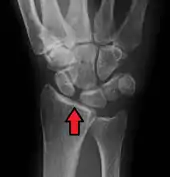

X-ray images indicate scapholunate ligament instability when the scapholunate distance is more than 3 mm, which is called scapholunate dissociation.[7] A static scapholunate instability is generally readily visible, but a dynamic scapholunate instability can only be seen radiographically in certain wrist positions or under certain loading conditions, such as when clenching the wrist, or loading the wrist in ulnar deviation.[6]

Static scapholunate dissociation